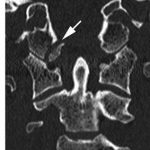

46歲男性單車手倒下導致頭顱枕骨髁骨骨折和頸椎C1-2韌帶損傷

他的頭顱和頸脊柱都不穩定, 由於頸椎神經損傷引起的手臂暫時性麻木

像前幾天86歲的老婆婆病人類似, 相同的腦神經外科醫生團隊,類似的手術,但這次涉及後頭顱枕骨要在他枕頭部位的頭骨上鉗入鋼片, 存在風險會損害他的小腦和主要靜脈血管竇 , 可引致中風或死亡.